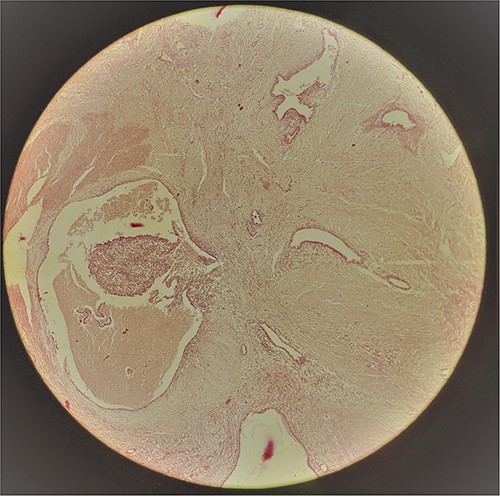

A 29-year-old female patient presented with a complaint of pain in lower abdomen for last 2 years. The pain would aggravate during menses. She also complained of a swelling at the site of her previous lower segment caesarean section (LSCS) scar for 1 year, which had gradually increased in size. She had underwent LSCS two and half years back. Nothing else was significant in history. Examination revealed a well circumscribed, firm mass at the surgical scar site, slightly to the right of the midline, ⁓6 cm × 5 cm in dimensions, fixed to underlying structures, especially on contraction of the rectus abdominis. Ultrasonography showed a heterogenous mass in the relation to the scar. Magnetic resonance imaging (MRI) revealed a well-defined heterogenous lesion extending into right rectus abdominus muscle, 4.2*3.1*2.2 cm in size with multiple thin septations within it, suggestive of scar endometriosis. Intraoperatively an irregular mass lesion was found in the subcutaneous scar tissue and was noted to be invading the rectus abdominis (Fig. 1). Enbloc excision of the endometrioma along with the involved portion of rectus sheath and rectus abdominis muscle was done (Figs 2 and 3). In view of potential tension on the fascial closure onlay mesh reinforcement was also done. The post operative course was uneventful and the patient was discharged on 7th post operative day. The histopathological examination confirmed the presence of endometrial tissue within the excised mass with skeletal muscle bundles infiltrated by endometrial glands (Fig. 3). Patient is on regular follow up and is recurrence free at 9 months.

The cut section revealing areas of haemorrhage, pointed out by the arrow.